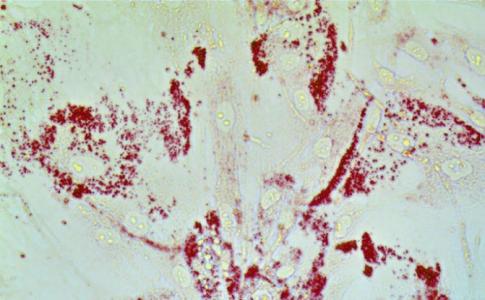

Les cellules cancéreuses (en rouge sur visuel) engloutissent les lipides. La protéine CAVIN1 redistribue les lipides en favorisant le microenvironnement du cancer ce qui déclenche l'inflammation et favorise le développement de la tumeur. La protéine régulatrice des lipides transmet ce que les chercheurs décrivent comme une « superpuissance » aux cellules cancéreuses de la prostate, les induisant à se propager de manière agressive.

L’étude in vitro, réalisée sur les cellules cancéreuses et humaines de la prostate et des lignées cellulaires stromales, montre que lorsque la protéine régulatrice des lipides CAVIN1 est retirée des cellules stromales ou fibroblastes (les cellules du tissu conjonctif dans et autour des tumeurs) les cellules cancéreuses vont chercher ces lipides dans leur environnement, les utilisant comme carburant, en particulier pour fabriquer des hormones qui nourrissent le cancer. Ces lipides alimentent ainsi leur propagation. Et dans toutes les lignées de cellules cancéreuses de la prostate testées, les cellules tumorales montrent cet appétit universel pour les lipides, les utilisant pour alimenter leur croissance, renforcer la membrane protectrice autour de la cellule, synthétiser des protéines et fabriquer de la testostérone pour soutenir la croissance du cancer. L’accès aux lipides de l’environnement apporte aux cellules tumorales plus de puissance : la tumeur est la même tumeur, mais son évolution change.